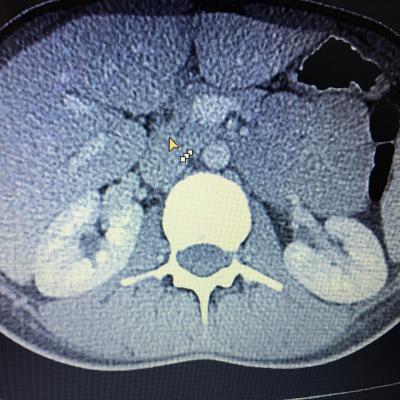

Здравствуйте,помогите, пожалуйста, с расшифровкой кт почек с контрастом. Насколько я поняла, в левой почке маленький камешек. А что за образование в правой почке? Киста с кальцинированной стенкой или камень? Спасибо за ответ!

Здравствуйте! На последнем снимке - больше данных за конкремент. Но при описании снимков должны определяться плотность образования, и нет изображения ни одного фрагмента ни одного из мочеточников. И самих снимков обычно бывает больше. Недостаточно данных для заключения.